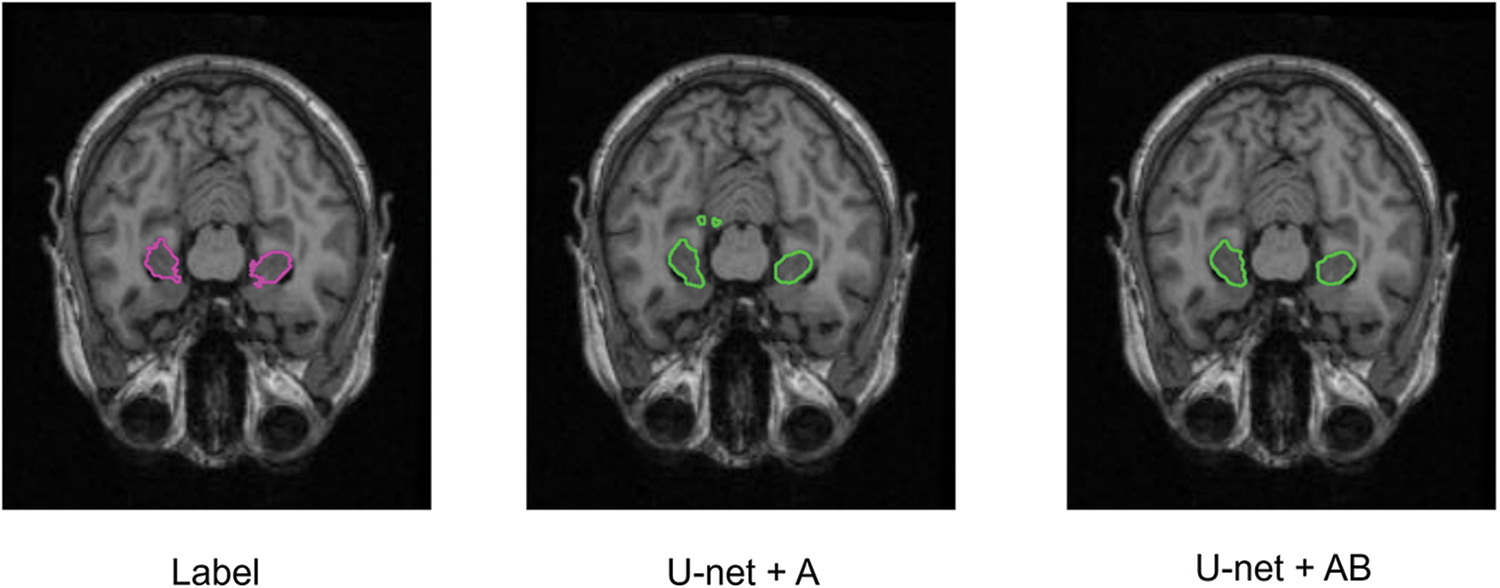

Ablation experiments are implemented to compare U-Net, U-Net+A, U-Net+B, and our proposed model in the same environment. Precision, Specificity, Sensitivity, SSIM, and Dice are used as evaluation indicators to further verify the effectiveness of our proposed model. Table 2 shows the comparison results. It can be seen that our proposed SC-Net outperforms the above models from ablation experiments. The Dice index has increased by

Figure 7: Segmentation of ablation experiment